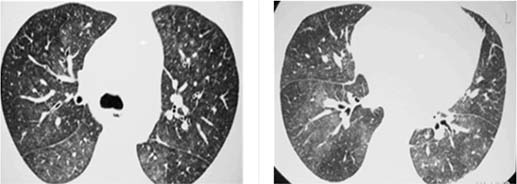

Um Paciente de 25 anos de idade, com tosse e febre de início súbitos 60 dias após transplante de medula óssea, realizou RT-PCR para Covid-19, cujo resultado foi negativo. Constataram-se exame de BAAR negativo, teste de Mantoux negativo e fibrobroncoscopia com cultura e BAAR negativos. A tomografia de tórax apresenta opacidades com atenuação em vidro fosco e pequenos nódulos pulmonares bilaterais, conforme as imagens a seguir.

Acervo Pessoal.